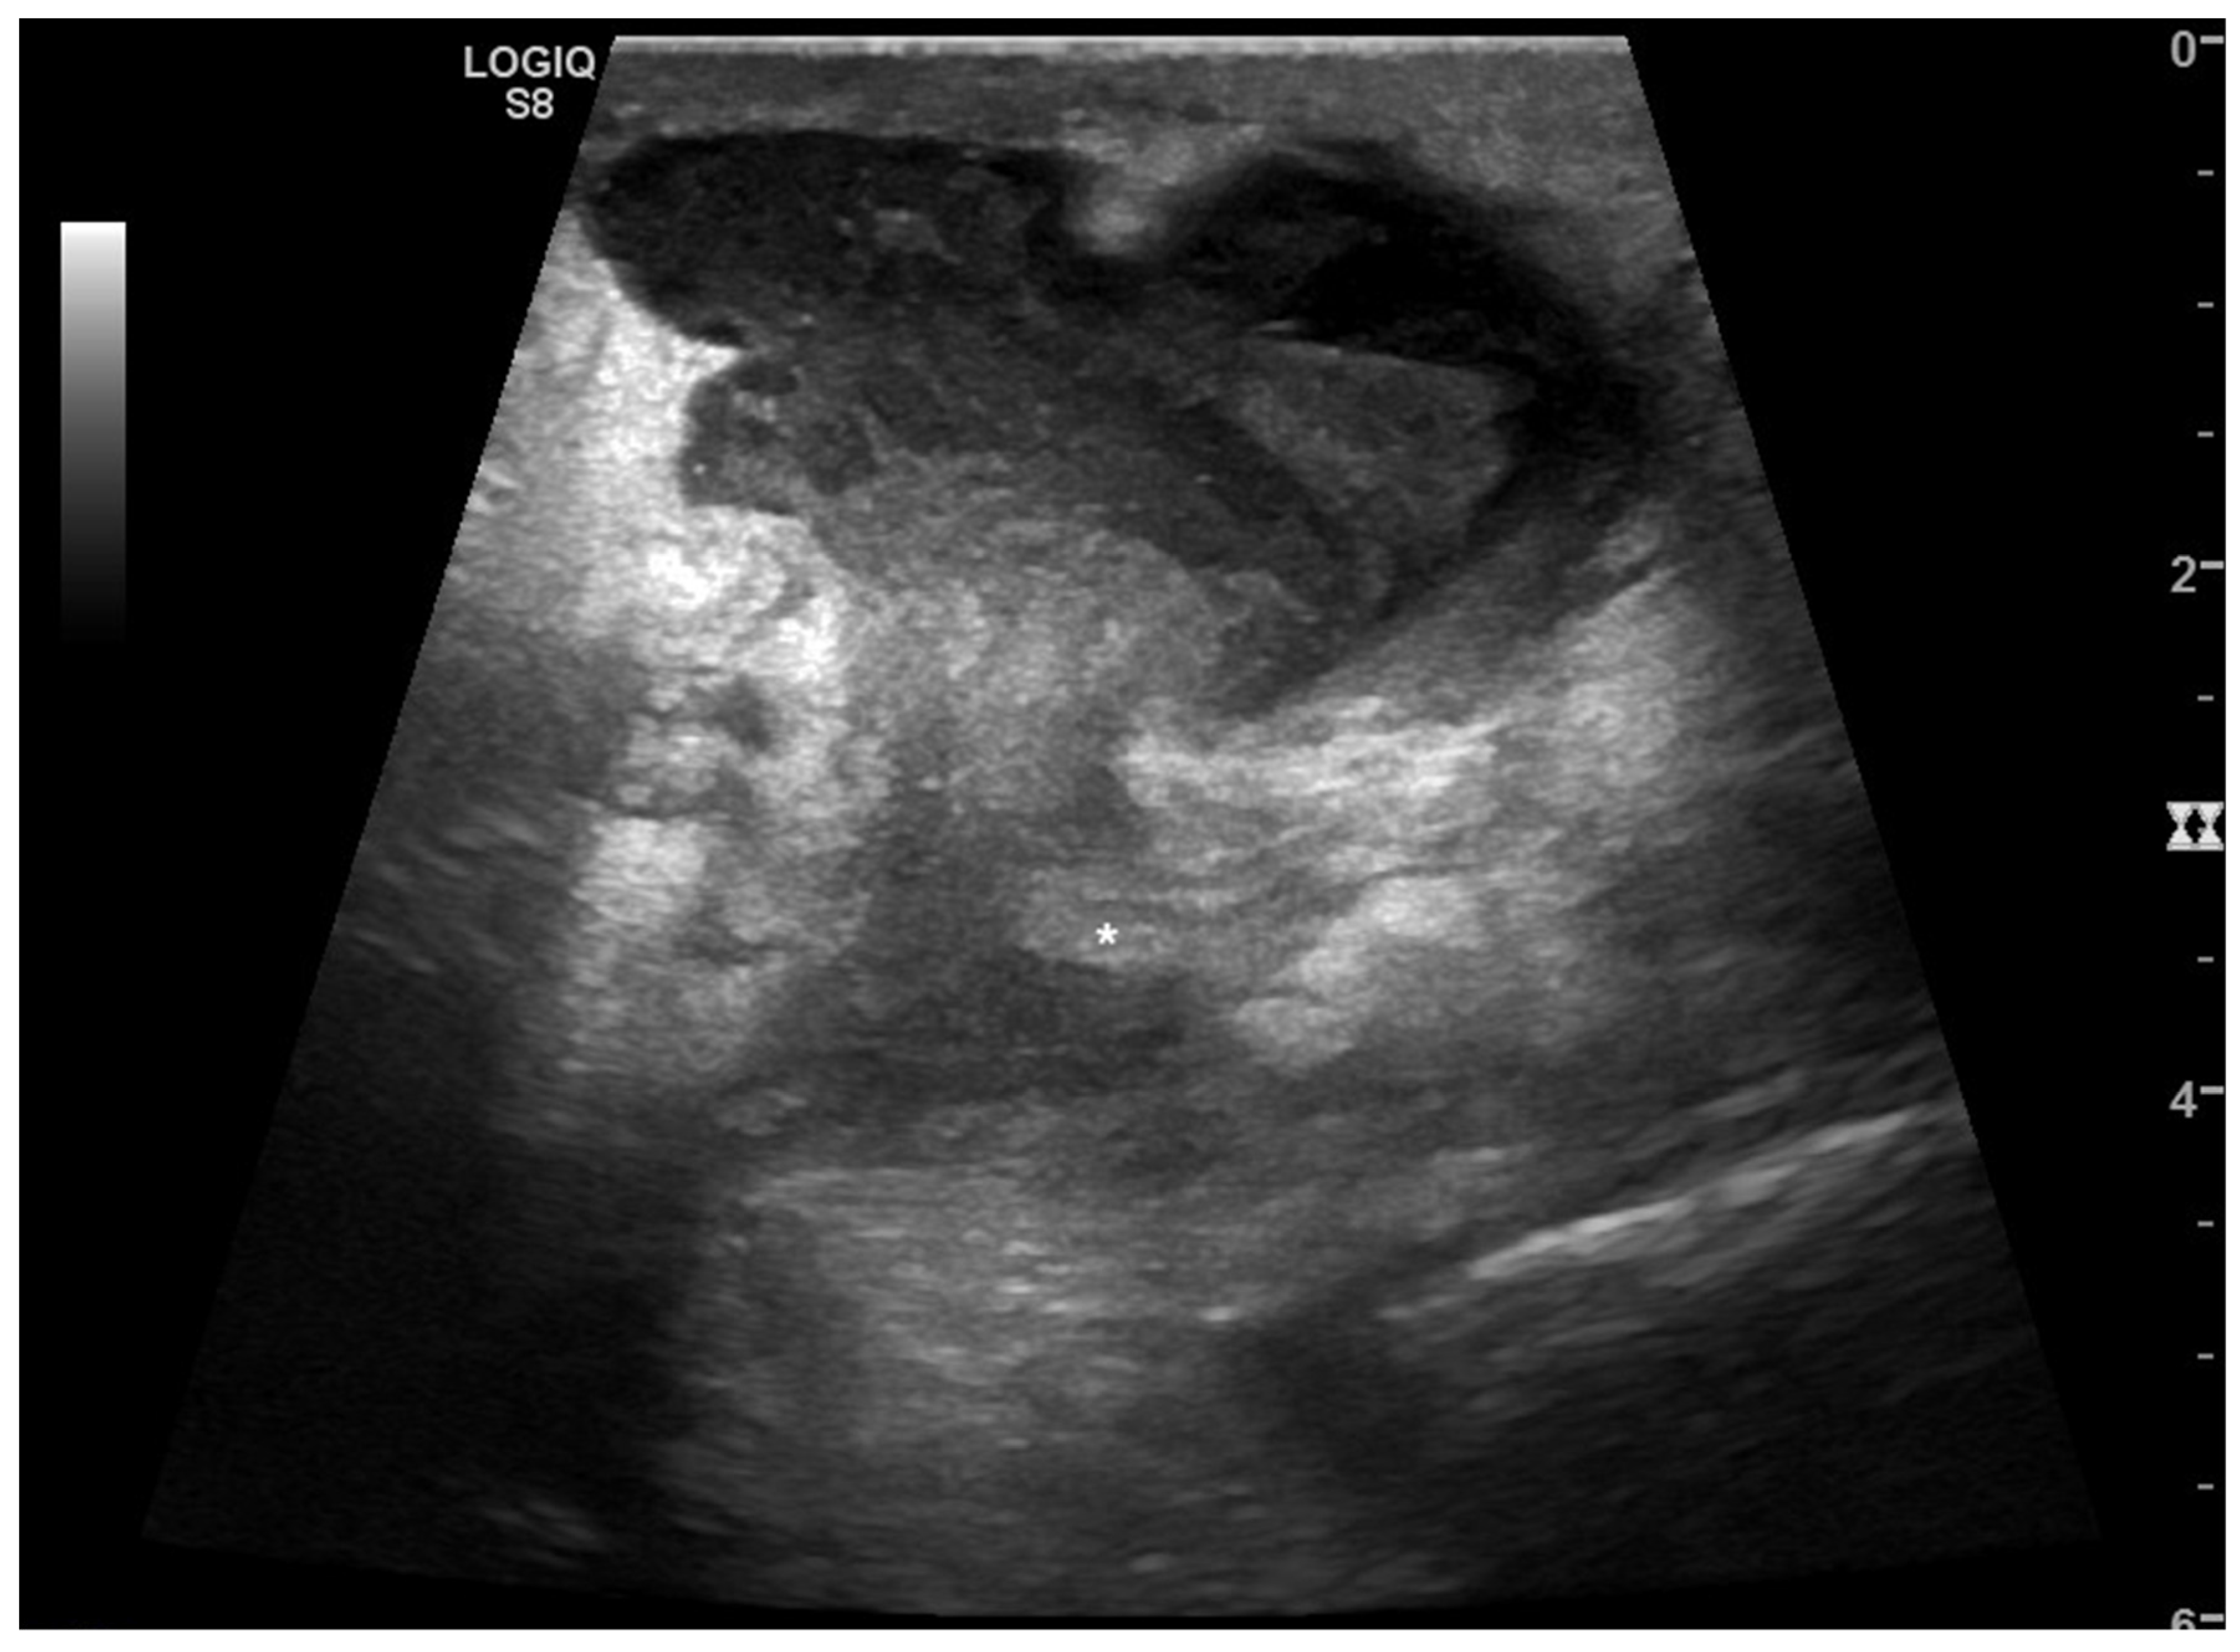

2.1.1. Non-Traumatic Hemoperitoneum

2.1.2. Non-Traumatic Free Fluid